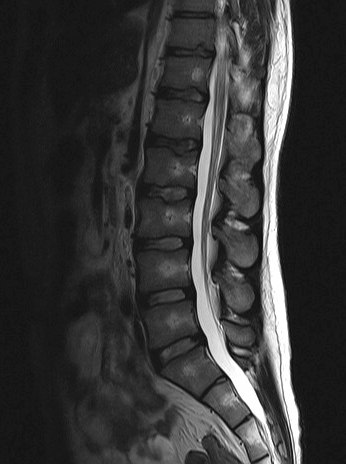

Mittlerweile hatte ich mit einigen teils schwerwiegenden Erkrankungen zu kämpfen, zu denen sich seit kurzem verschiedene neurologische Symptome, Rückenschmerzen, Mißempfindungen etc. dazugesellten. Ich wurde zum Rücken-MRT (vom Neurologen) geschickt wegen Verdacht auf eine entzündliche Erkrankung des ZNS. Leider wurde aus Abrechnungsgründen statt der gesamten WS nur die LWS gemacht. Hier kam heraus, dass sich die Skoliose auf 16 Grad mehr als verdoppelt hat. Außerdem kam wohl eine Hyperlordose 15 Grad?? dazu. Die Aufnahme von vorn sieht jedenfalls ziemlich krumm aus. Wie der Rest meiner WS aussieht weiß ich leider nicht

Zusätzlich multiple Schmorlsche Wirbelknoten, welche es vor 6 Jahren noch nicht gab... leider kann ich nur ein Bild anhängen, die anderen bekomme ich iwie nicht als jpg. gespeichert...

Der Radiologe sagt alles normal, sei ein alter Scheuermann... aber den hätte man doch sicher vor 6 Jahren schon erkannt, auf den alten Bildern sieht alles schön sauber aus, auf den neuen naja ich weiß nicht... irgendwie schon anders oder was meint ihr...? Kann man auf dem Bild etwas sehen ob wirklich alles ok ist? Und wenn nicht, was kann ich dagegen tun? KG alleine scheint nicht sehr effektiv zu sein?